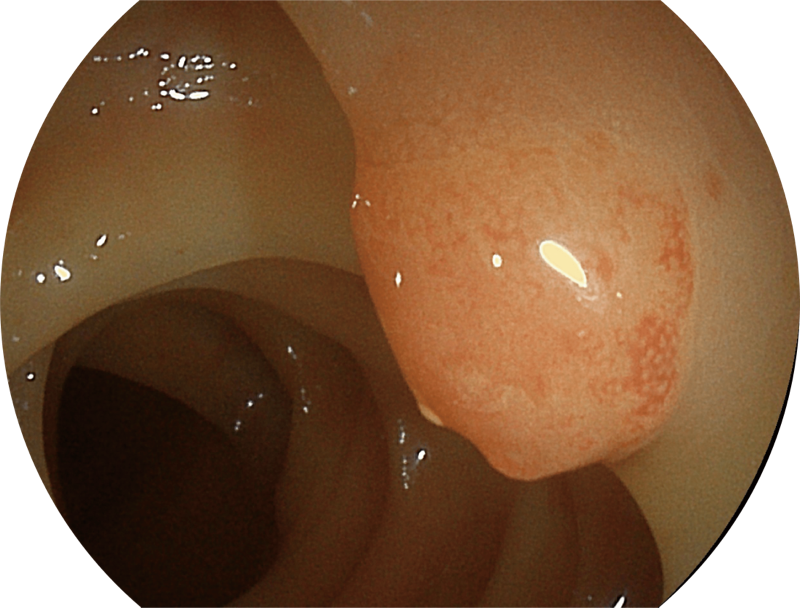

白光图像

SFI图像

能够凸显黏膜浅层血管轮廓和黏膜表面微结构,适用于中、近景观察下的早癌精确诊断。